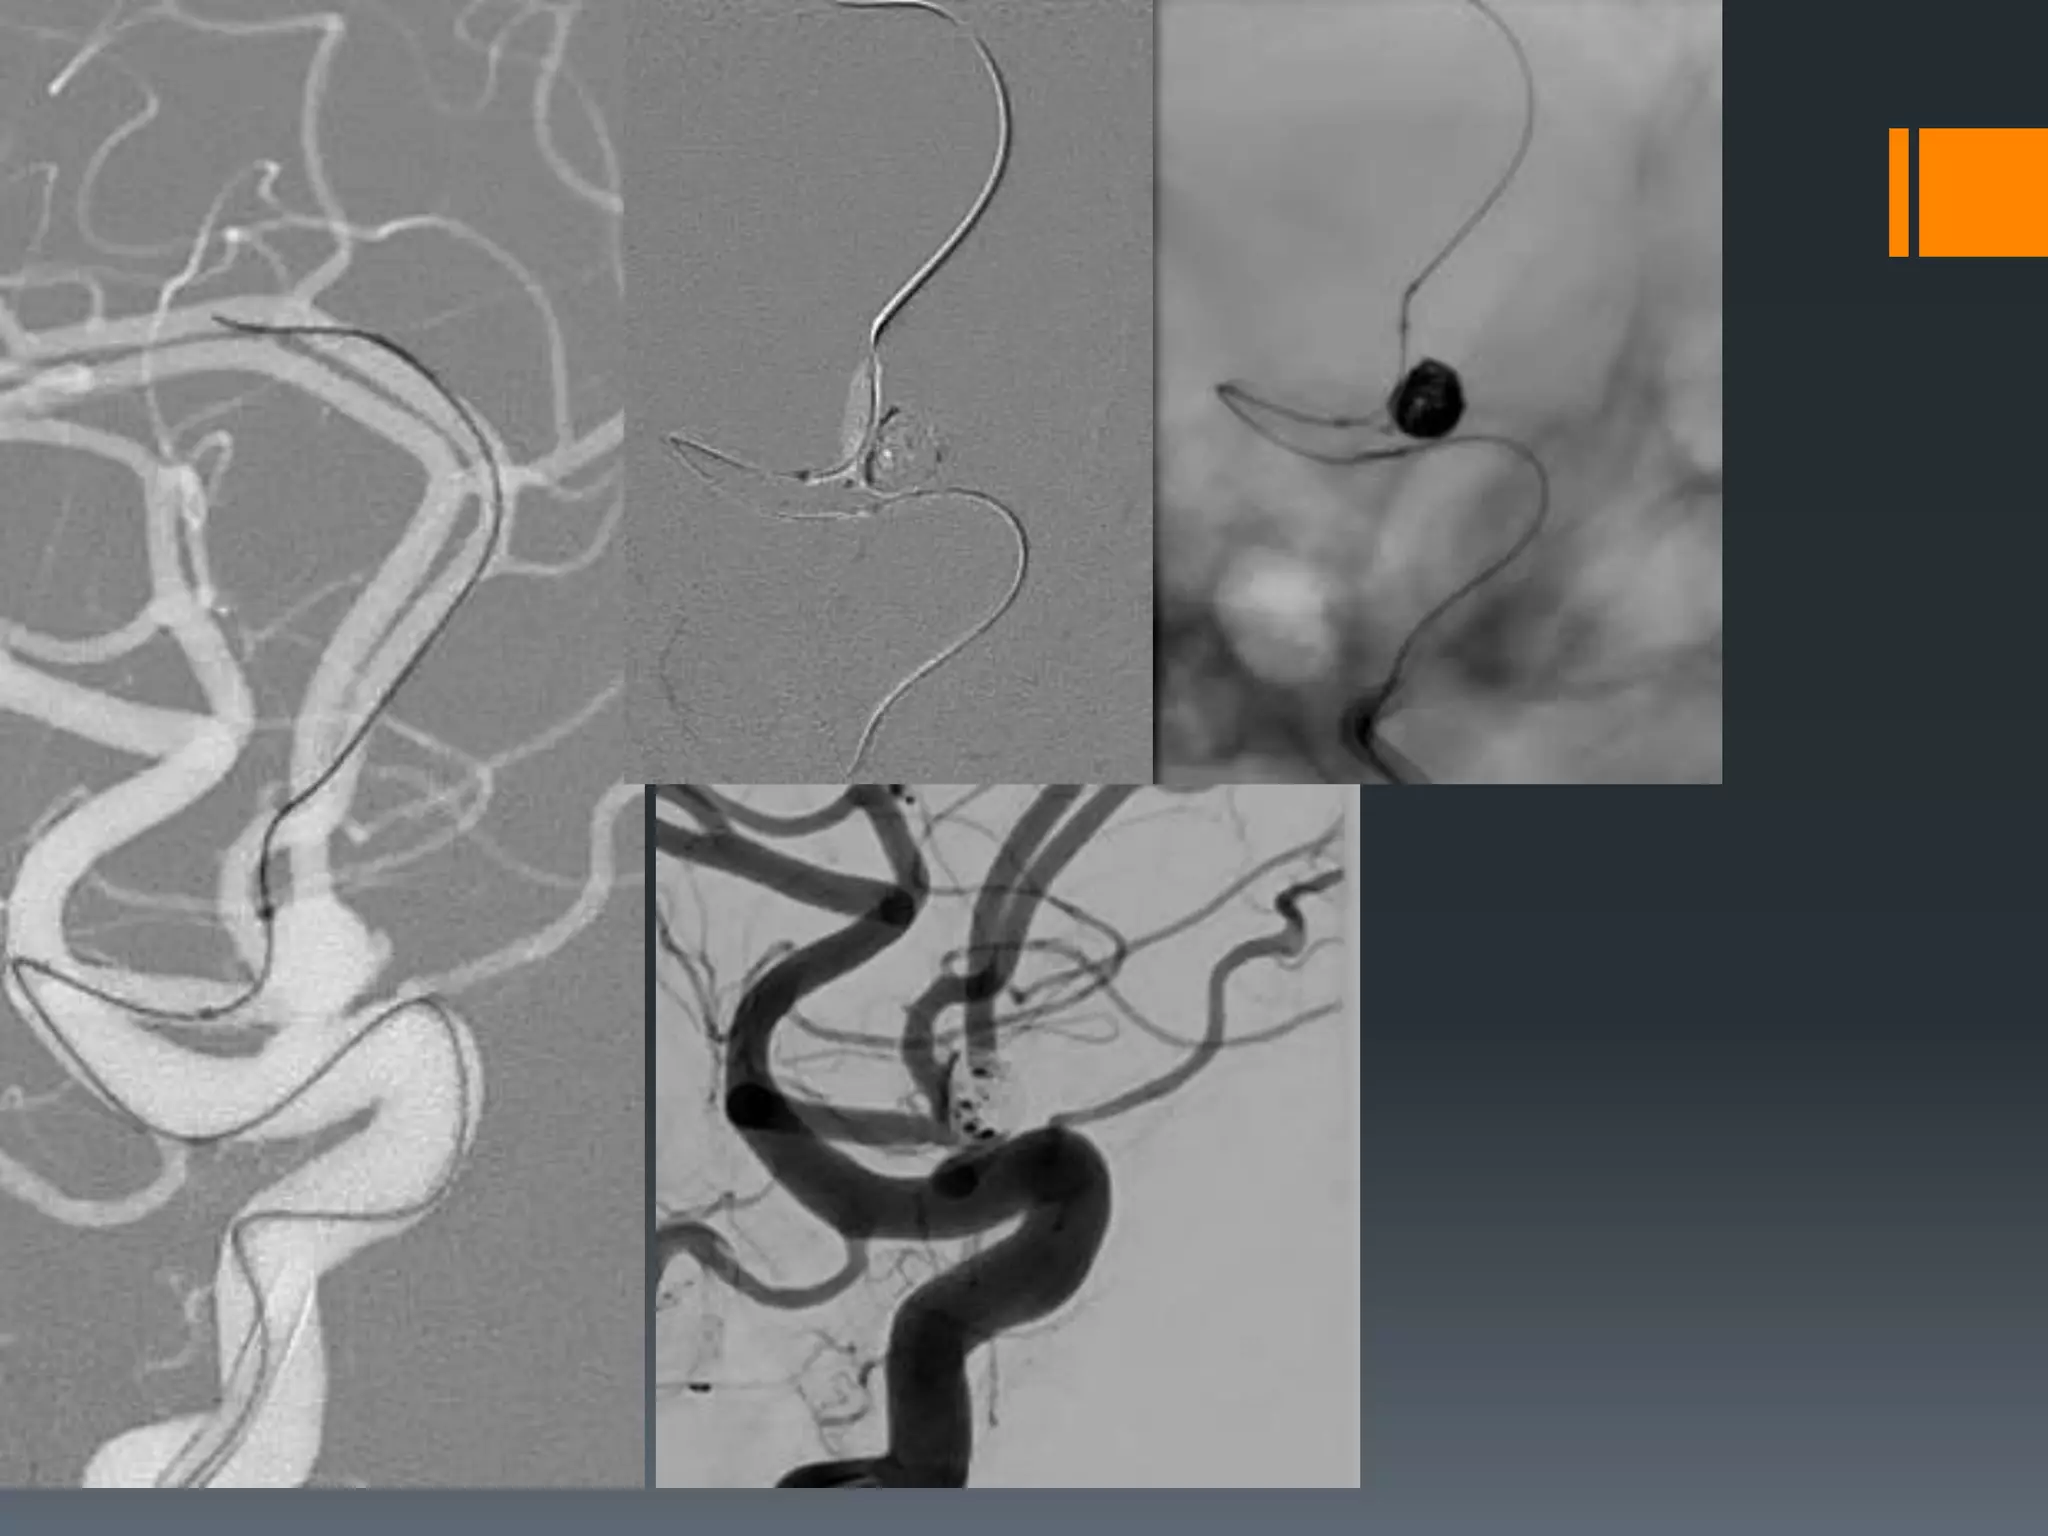

This document discusses tricks and techniques for difficult cannulations during neurointerventional procedures. It outlines strategies for accessing the aortic arch, internal carotid artery (ICA), and areas distal to aneurysms. Long sheaths, distal access catheters, and co-axial techniques are presented as options that have improved cannulation success. Guidance on sheath and catheter selection is provided for different vessel paths. The importance of catheter placement as high as possible in the ICA is emphasized. Reverse curve cannulations are also mentioned. Overall, the document stresses that careful cannulation is critical for procedural success and different strategies may be needed depending on the vessel target.